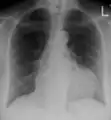

The diagnosis of tamponade can be confirmed with trans-thoracic echocardiography (TTE), which should show a large pericardial effusion and diastolic collapse of the right ventricle and right atrium. Chest X-ray usually shows an enlarged cardiac silhouette ("water bottle" appearance) and clear lungs. Pulmonary congestion is typically not seen because equalization of diastolic pressures constrains the pulmonary capillary wedge pressure to the intra-pericardial pressure (and all other diastolic pressures).

Ultrasounds showing a pericardial effusion in someone with pericarditis

A pericardial effusion as seen on CXR in someone with pericarditis